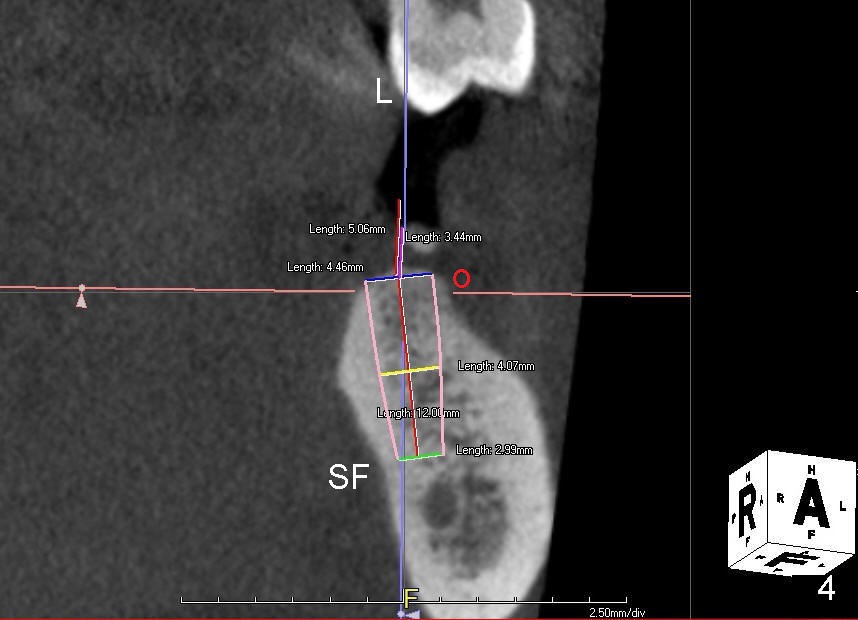

Traditionally, implant placement concentrates upon not touching the neighboring root or the nerve (Fig.1 (CT sagittal section), 2 (coronal) N) and inside the buccal and lingual plates (Fig.2 B, L). The design does not consider opposing dentition.

Probably due to long standing edentulism, the buccal plate is atrophic. In order for the future crown (mainly its buccal cusp) to occlude with the lingual cusp (Fig.4 L, functional cusp) of the upper 2nd molar, the coronal end of the bone-level implant should be more buccal than the traditional one (Fig.2), whereas the apical end more lingual. But not too much! The lingual plate should be protected. Place a finger in the submandibular fossa (SF) while making osteotomy.

Root canal therapy has been done for the tooth #19. Before surgery, take a PA using the existing layout to confirm that the apical radiolucency has been reduced or disappeared. After finishing 2 mm pilot drilling at the depth 8 mm, insert a paralleling pin and check the trajectory against the upper opposing tooth. Make necessary adjustment with Linderman bur. Then take PA to check mesiodistal trajectory and proximity to the nerve. Deepen osteotomy to 12 mm (deeper than 11 mm mark). Use reamers for further osteotomy. The autogenous bone will be saved and placed most likely in the buccal aspect when the buccal threads are exposed (Fig.4: red circle). Use collagen dressing (apron-shaped with a hole in the middle, buccal portion wider). Use a 5.2 (or 6.2 mm) healing abutment to hold the dressing in place. From Fig.4, can you guess what length and cuff should be chosen? How is the result?